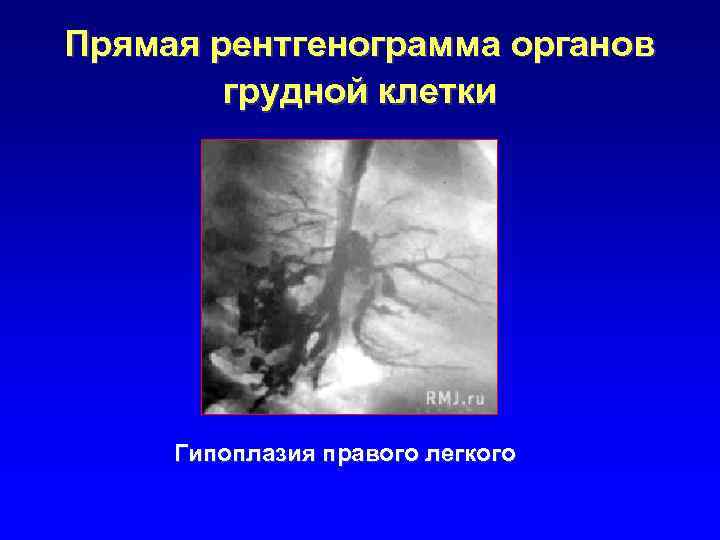

Прямая рентгенограмма органов грудной клетки Гипоплазия правого легкого